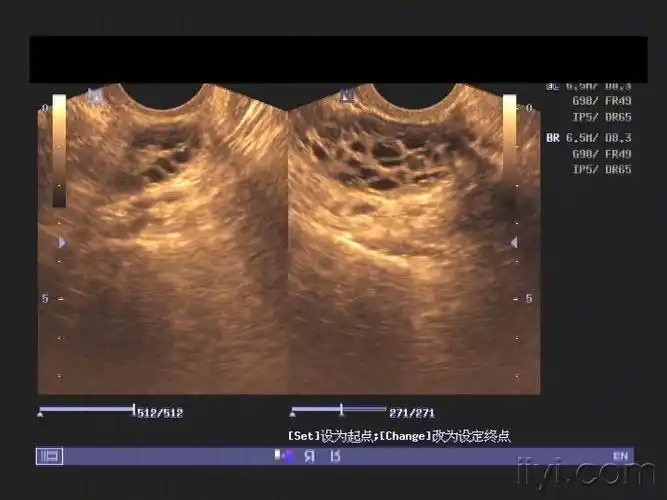

沉甸甸!双侧卵巢多囊样改变严重吗"可以选择"-第2张图片-飘零博客

3,多囊卵巢,单侧或双侧有大于或等于12个小卵泡.

(双侧卵巢呈多囊样改变)该怎么治?白带拉丝一定排卵吗?